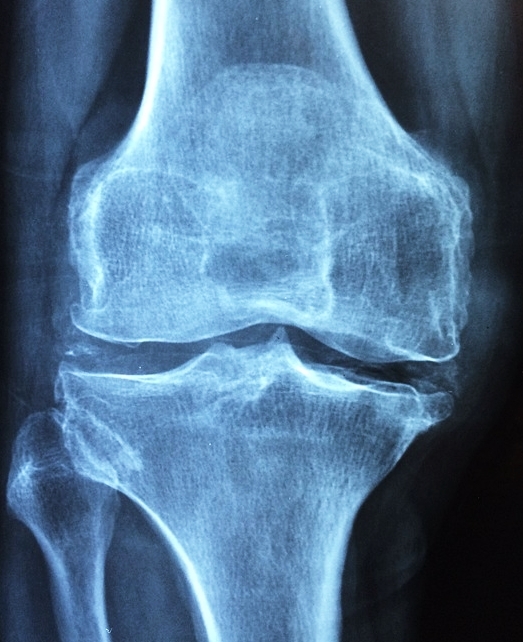

3. 계단을 오르거나 걸을 때 무릎이 아프다

퇴행성 관절염의 초기 신호 중 하나는 계단을 오르내릴 때 무릎이 뻐근하거나 통증이 느껴지는 것입니다. 관절을 움직일 때 연골이 마찰을 줄여야 하지만, 연골이 손상되면서 뼈끼리 부딪히는 느낌이 들 수 있습니다.

평지에서는 괜찮지만 계단을 오르거나 앉았다 일어날 때 통증이 심해진다면 관절염 초기 단계일 가능성이 높습니다.